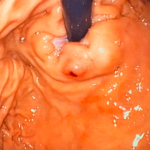

Desde el punto de vista morfológico y etiológico, los divertículos duodenales pueden clasificarse de varias maneras: como congénitos o adquiridos, verdaderos o falsos, y como intraluminales o extraluminales. Los divertículos extraluminales son los más frecuentes. Estos son generalmente adquiridos y consisten en herniaciones de la mucosa y la submucosa a través de un defecto de la capa muscular, lo que refleja un proceso degenerativo o de debilidad focal en la pared intestinal. Por el contrario, los divertículos intraluminales, también denominados “divertículos en manga de viento”, son raros y congénitos, originados por una recanalización incompleta del lumen duodenal durante el desarrollo embrionario, dando lugar a una estructura sacular aislada que se conecta parcial o completamente con la circunferencia del duodeno. Este mecanismo explica su baja frecuencia y su presentación anatómica compleja, que puede formar estructuras tipo malla dentro del lumen intestinal.

En cuanto a su localización, los divertículos extraluminales muestran una distribución característica: predominan en la segunda porción del duodeno (alrededor del 62%), en particular en la región periampular, donde el 88% se localiza en la pared medial, próxima a la ampolla de Vater. La tercera porción alberga aproximadamente un 30% de los casos y la cuarta porción solo un 8%, mientras que los divertículos en la primera porción son excepcionales, con una frecuencia menor al 1%. Esta distribución refleja tanto la anatomía vascular y muscular del duodeno como la presión intraluminal diferencial, que favorece la formación de divertículos en zonas donde la pared intestinal es relativamente más débil.